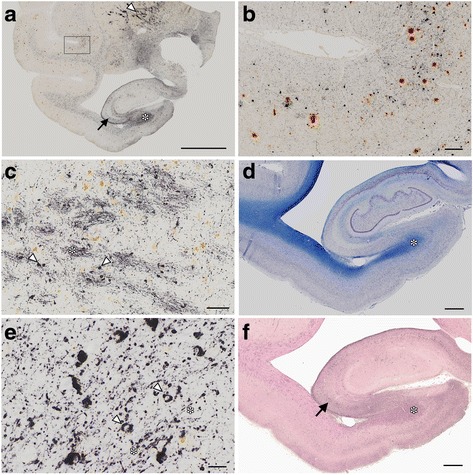

In this cohort, deposits immunoreactive for Aβ were found in brain sections from primates 24 years of age and older, while deposits immunoreactive for PHF-tau (AT8) were found starting at 30 years of age (Table 1). The brain from the oldest monkey we examined (36 yo) exhibited numerous tau deposits (dark purple, Fig. 1a, b) as well as Aβ deposits (brown, Fig. 1a, b). Pyramidal neurons in the hippocampus exhibited AT8 IR (Fig. 1a, arrow). Because tau-positive deposits were abundant in the white matter (Fig. 1a, d, asterisks) and basal ganglia, (Fig. 1a, arrowhead) particularly in the globus pallidus (GP, c), their distribution was different from that of AD in the human brain, which is prevalent in the hippocampus.

In the GP, AT8 immunoreactivity (IR) was found in fiber bundles (asterisk, c) and small round cells, likely to be oligodendroglia (arrowheads, c. See Fig. 4 for more details). AT8 IR was also abundant in the white matter in the temporal lobe (a, asterisk) and the hippocampus (asterisks in a and d). Higher magnification of the hippocampal white matter (e) identified AT8-positive oligodendroglia-like cells (arrowheads, e) and fibers (asterisks, e). Adjacent hippocampal slices demonstrated 4R tau (RD4, Fig. 1f) IR in pyramidal neurons (arrow, Fig. 1f) and in the hippocampal white matter (asterisk, Fig. 1f). Because 3R tau IR was absent in these AT8/RD4-positive lesions (data not shown), their staining profile was different from that of human AD, which is immunopositive for both 3R and 4R tau [ref. 11, ref. 12]. At higher magnifications, AT8 (Fig. 2a) and RD4 (Fig. 2b) tau immunoreactivity was diffuse and granular in the neuronal cytoplasm and dendrites, and rarely organized into NFTs. Argyrophilia with Gallyas silver impregnation was quite limited (Fig. 2c, arrowhead) and they were not argyrophilic with Campbell-Switzer silver impregnation (data not shown). The scarcity of NTFs, fibrillary structure, and Gallyas silver argyrophilia, also differs from AD pathology in the human brain (Fig. 2d, arrowheads).

We observed numerous AT8-positive processes (Fig. 3a, dark purple, arrowheads), independent of Aβ (Fig. 3a, brown, asterisk) in the temporal cortex. Similar structures in the same area were positive exclusively for RD4 (Fig. 3b) and oriented around blood vessels (Fig. 3b, arrows). Thorn-shaped astrocytes or granular/fuzzy astrocytes grouped under the umbrella of “aging-related tau astrogliopathy” were not apparent in these monkey brains [ref. 22]. AT8-positive oligodendroglia-like cells and threads were abundant in GP (Fig. 4a) and in the white matter (Fig. 1e). Both perikarya and threads of these oligodendroglia-like cells were positive for both Gallyas silver impregnation (Fig. 4b), and RD4 (Fig. 4c) in adjacent sections, but consistently negative for 3R (Fig. 4d). In summary, AT8/RD4-positive neurons were pretangle-like but their distribution was accentuated in pyramidal neurons of Ammon’s horn (Fig. 1a and f arrow) as in AD. However, AT8/RD4-positive glial cells in the hippocampal white matter (Fig. 1a, d and f asterisks) and basal ganglia were conspicuous.

Tau-positive lesions were particularly numerous in the oldest monkey examined (36 yo Fig. 1). However, these cytopathological findings, including pretangle forms of tau in neurons, tau-positive astrocytes, and inclusions in oligodendroglia-like cells, were also detected in brain sections from other monkeys older than 30 years of age (Fig. 5). Similar to the 36-year old monkey, tau-positive lesions were seen more frequently in the neocortex than in the hippocampus (Fig. 5).